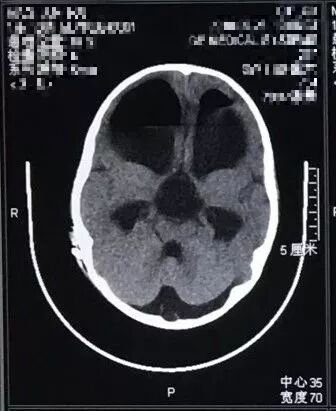

检查头颅磁共振如图:

![]()

可见鞍上池蛛网膜囊肿,并堵塞室间孔和中脑导水管上口导致脑积水。